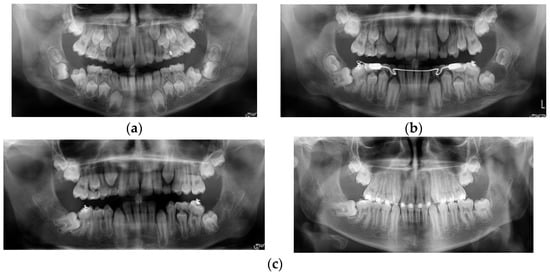

At a routine X-ray exam, it was noted that the right upper canine with a DC was in a very high position in the bone, mesially inclined, in transposition with the upper first premolar and in closed contact with its apical half of the root, which was already dilacerated, with a mesioangulation (Figure 1a). This position could be a risk factor for canine impaction. Because of the lack of space and crowding, after the extraction of right deciduous molars (to facilitate the eruption of the premolars), the first step of the treatment plan was maxillary expansion, which could have also been a preventive method of canine impaction.

(a) Initial panoramic X-ray showing the upper right canine in a very high position and transposition with the first premolar. (b,c) Different types of root DL affecting right premolars. No improvement regarding the position of the right canine after maxillary expansion. (d) The upper left second premolar also has a root DL.

After maxillary expansion, the first premolar partially erupted, but the second one was impacted due to the lack of space and both distally inclined and completely formed roots. The roots of the premolars had different types of DLs, from a slight flexion of the second premolar’s root to a true dilacerated root of the first premolar. The canine remained in the same position while the DC was still growing (Figure 1b).

To obtain more space for upper premolars and canines, the patient wore a low pull headgear to distalize the upper first molar and then fixed appliances to fulfil the objective of the orthodontic treatment. Because the canine did not change its position (Figure 1c), marsupialization of the cyst was tried, and consequently, the canine started to erupt between the roots of the first premolar. At this moment, it has been decided to incline the roots of the first premolar distally to prevent root resorption by the canine.

Regarding the cause–effect association between DC and root DL, in this case, DC could be the cause of root DL (taking into consideration the initial high and mesioinclined position of the canine, in transposition with the first premolar, along with its DC that had continued to grow, in closed contact with the apical half of the first premolar root, the DLs of first premolar root as the flexion of the second premolar root). This could be explained by the pressure applied by the cyst on that area of dense bone structure. The last panoramic X-ray (Figure 1d) showed a root DL of the second upper left premolar. Thus, the DL could have another cause, namely a genetic one, as a dental anomaly pattern (DAP) or associated dental anomaly (ADA), in which many dental anomalies coexist, as in this case, the canine impaction, transposition, DC, and root DL. The root DL of the impacted canine could also be seen on the CBCT (Figure 2a,b).

A lingual arch was placed to maintain the position of the first mandibular molars. Extraction of deciduous mandibular molars and the marsupialization of the cysts were performed. After surgery, all impacted teeth started their eruption in an appropriate position. Although the left first premolar changed its position to a normal one, there was not enough space for its eruption in addition to having a root DL (Figure 4c).

The left lateral incisors and canine also had small degrees of root DL. As was stated previously, the cause of the DCs could be the pulp infection of the deciduous molars, but there were differences between the two DCs and local conditions. The right DC was of inflammatory origins, and after the marsupialization, the premolar started to erupt in its normal position. On the left side, the cyst is bilocular, and the inflammatory origin could not be the only etiological factor. There are also other dental anomalies, supernumerary teeth, and the different degrees of root DL affect not only the tooth associated with the DC but also other teeth from that area. This clinical case is a DAP case.

A 9-year-old boy came for orthodontic treatment because of the protrusion of his upper incisors. A trainer was recommended for him, but he could not manage it. The patient had a class II div 1 Angle malocclusion, mixed dentition with a delayed eruption of the permanent teeth, and the absence of the first mandibular molars. On the panoramic X-ray, it was noted that the rest of the permanent teeth on the right side (including the third molars), the first and second mandibular molars were impacted and associated with a sizeable DC, with the development of the roots delayed, and the first molar was dilacerated. On the left side, the situation was almost the same, with both the first and second molars being impacted and associated with DC. The roots of the molars were in an early stage of development, uncorrelated with the patient’s age (Figure 5a). As in all previous cases, the treatment objective regarding the DC-associated impacted teeth was to try to preserve the teeth. Therefore, the cyst’s marsupialization was done, followed by monitoring of the patients. Six months later, although the first permanent molars started to erupt slowly, orthodontic traction from a bonded attachment was applied to bring the teeth intraorally (Figure 5b). The DC of the left second molar continued to grow, blocking the molar’s eruption and the development of its roots. On the right side, the second molar became more horizontally positioned in the bone under the crown of the first molar. We decided on another marsupialization of the cyst-associated second left molar and extraction of both mandibular third molars. After four months, the left second molar was erupting in an optimal vertical position. The right second molar was still almost horizontally impacted, without any bony defect, due to DC (Figure 5c). At that moment, both first mandibular molars were in the oral cavity, well aligned in the lower arch, but not in the appropriate one, because of the roots DL. There was also a slight root flexion of the right mandibular canine.

(a) Bilateral impaction of lower first and second molars associated with DCs. All four molars presenting abnormal root development, uncorrelated with the age of the patient. (b) Orthodontic traction applied from a lingual arch to aid the eruption of the lower first molars. (c) Progress records at four months after the removal of both mandibular third molars.

The aforementioned is a rare case of bilateral mandibular DC-associated first and second molars, impaction, and root DL of the first molar. The DCs could be the cause of a root DL because the tooth did not erupt, and the roots were constrained to develop in a closed area of dense bone. Another factor that could determine the first molar’s root DL was the pressure applied by DCs of the second molar’s and probably the third molar’s buds. Because the root DL also affected the canine, it could also be considered the genetic etiology of root DL in a DAP patient.